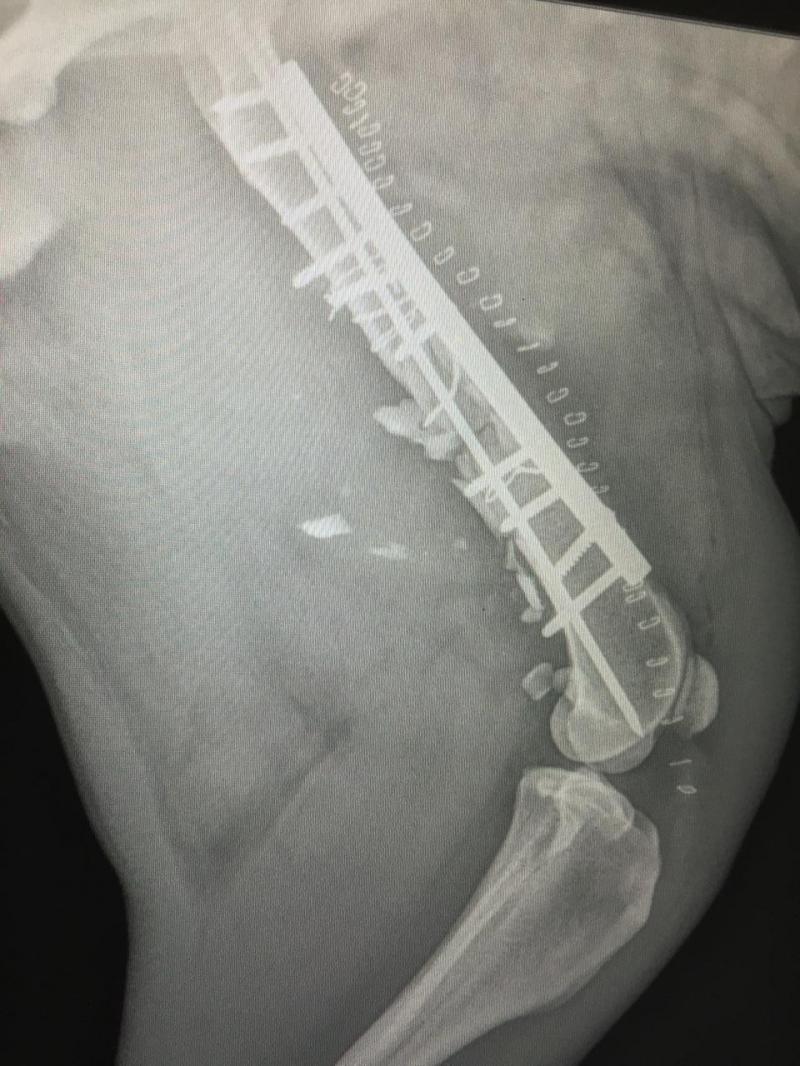

Spinal disc repair surgery, 5lb Chihuahua. (Post-op rehab photo in PHOTOS)